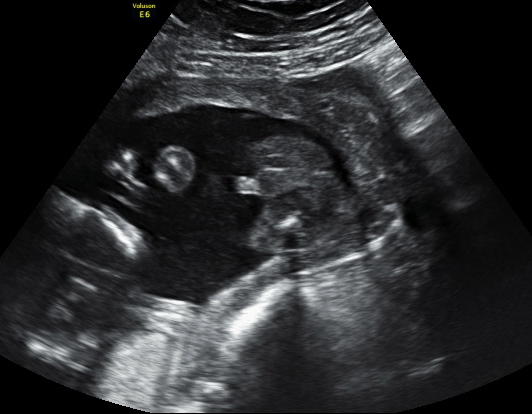

Hello Ladies, So here is my 19 wk+2 days scan shot. We intentionally didn't ask her for the gender as i was not sure how i will handle if there was a disappointment. But i did request her for some shots which might give us a clue. So here are some pictures. The first one i am not sure if it is a potty shot but i can't think what else it can be. So let me have your guesses please. Eagerly waiting.

Attachment 17334

A beautifull :DS: congrats!

Boy!!!!! Looks like your sway was successful congratulations xx

:DS: !!!!

BOY!!! so excited for you!!

Thank you everyone. Any more guesses please. Can i start buying blue then??

Here is the think YY - I totally think it's a boy, but none of us are techs and there is only one pic. So while we all think it's a boy and I feel pretty confident, I am not in a position to say "yes I am sure" . So I will just say I am as sure as a non-expert is able to be on the basis of one picture, but just take it with a grain of salt because it's best to go off opinions of techs who get to look at the goods for several minutes.